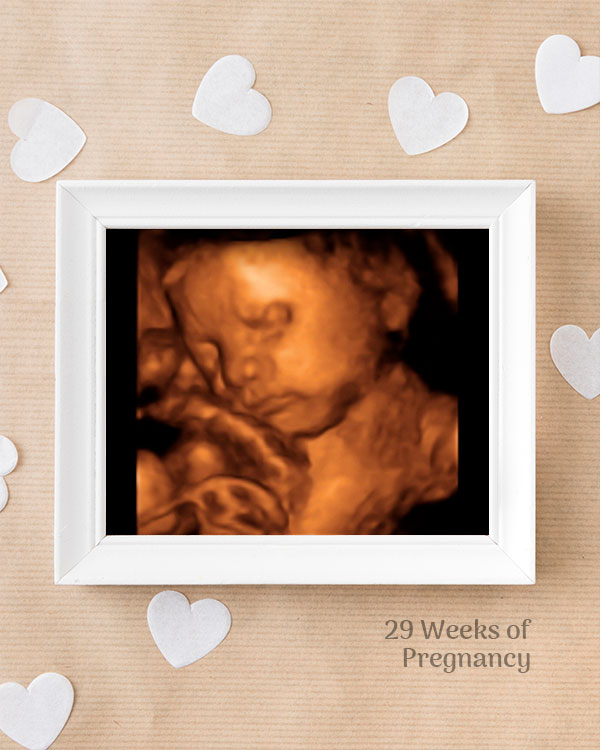

3D / 4D Baby Scan

Mediserv Diagnostics pioneered 4D scanning in the Malabar region. These advanced scans provide realistic images of the baby, allowing detailed evaluation of fetal structures and movements while creating a meaningful bonding experience for parents.